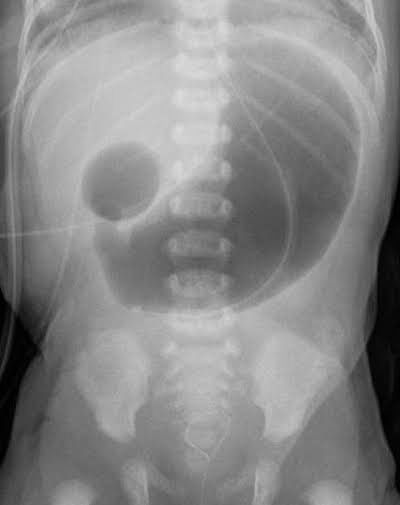

Duodenal atresia is a congenital anomaly of GIT in which the duodenum is malformed. The portion of the duodenum is either absent or completely closed which results in complete obstruction of duodenum. This can be clinically seen on X-ray as a double bubble sign. This sign is formed as a result of distension of stomach and duodenum due to entrapment of air in them. Both the structures are separated by the pyloric sphincter which makes it look like a double bubble on abdominal X-ray. Picture credit: https://en.m.wikipedia.org/wiki/Duodenal_atresia